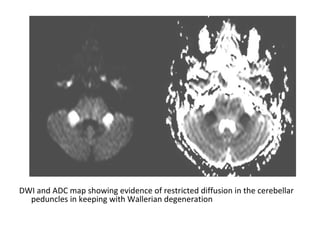

DWI and ADC map showing evidence of restricted diffusion in the cerebellar

peduncles in keeping with Wallerian degeneration